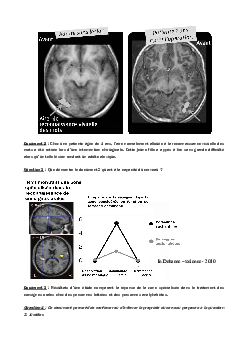

Représentation visuelle - Activité 7 (La plasticité cérébrale)